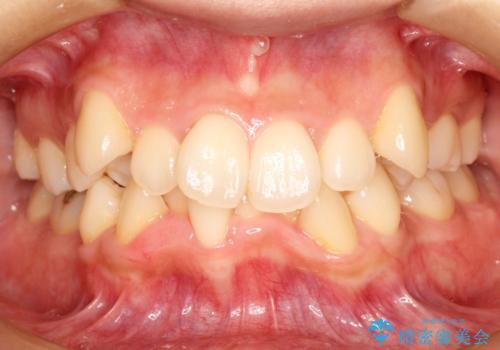

前歯の部分矯正 インビザラインエクスプレスパッケージ

- 再矯正希望で来院された患者様です。

再治療ということもあり、あまり費用かけずに後戻りを治したいというご希望がありました。

枚数限定のエクスプレスパッケージによる前歯のみの部分矯正治療を計画しました。

部分矯正は治療が短期間で終わる、費用が安いというメリットがありますが、時に治療において理想的な結果を目指せないことがあります。

今回は再矯正ということもあり非常に満足いただくことができました。